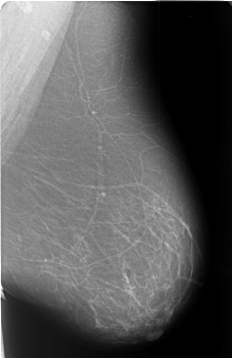

Digital Database for Screening Mammography

Volume: benign_13 Case: B-3443-1

B_3443_1.LEFT_MLO

LEFT_MLO LINES 5720 PIXELS_PER_LINE 3704 BITS_PER_PIXEL 12 RESOLUTION 50 NON_OVERLAY

FILE: B_3443_1.RIGHT_MLO.OVERLAY

TOTAL_ABNORMALITIES 1

ABNORMALITY 1

LESION_TYPE MASS SHAPE LOBULATED-IRREGULAR MARGINS MICROLOBULATED-ILL_DEFINED

ASSESSMENT 4

SUBTLETY 4

PATHOLOGY BENIGN